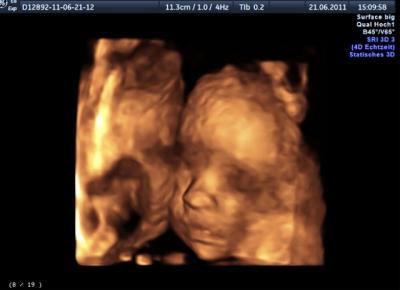

halli hallo! so nachdem wir am freitag vom urlaub zurückgekommen bin und ich mich erst wieder zu hause "eingewöhnen" musste, mich hier durchlesen musste und überhaupt viel zu tun hatte, war ich heute beim 3D ultraschall (hab ich von meiner mum zum geburtstag geschenkt bekommen) und ich bin soooo verliebt in meinen kleinen bauchpiraten und es bleibt definitiv bei einem jungen!

Bild zu 3D ultraschall - Forum für September - Mamis

ich hab mich auch total über dieses geburtstagsgeschenk gefreut, denn was schenkt man denn heutzutage wirklich noch??? wenn man etwas braucht kauft man es sich meistens sowieso selbst und so hatte ich etwas davon und mein freund auch. ein 3D kann man wirklich mit einem normalen ultraschallgerät nicht vergleichen, man sah alles sooo genau, wie er am daumen gelutscht hat, den mund auf und zu machte einfach herrlich und jetzt wo ich ihn gesehen habe freu ich mich noch mehr auf ihn. 13 wochen noch dann darf ich ihn im arm halten meinen kleinen prinzen!